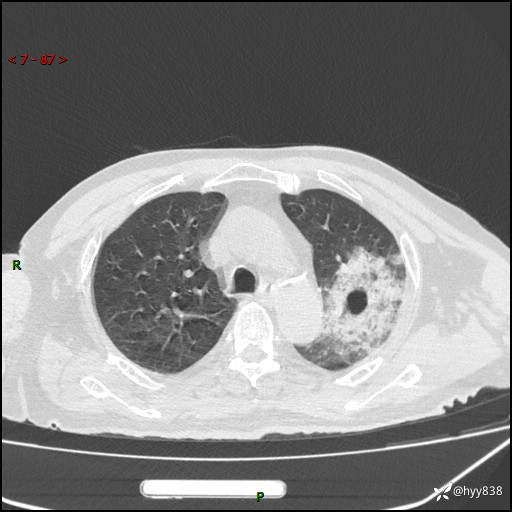

胸部CT复查(2024.8.5)